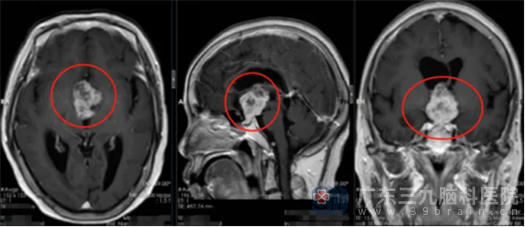

待患者病情稳定,进一步完善头颅MR,结果提示患者鞍上区占位性病变突入三脑室,其内存在囊变出血可能。鲁明初步考虑是偏良性肿瘤性病变伴瘤卒中的可能性大,考虑是毛细胞星形细胞瘤可能,待排颅咽管瘤等。

征得患者及家属同意后,鲁明带领神经外五科团队在全麻下为患者行右侧翼点终板入路肿瘤切除术。显微镜下见肿瘤组织呈灰白色,血供一般,质地一般,有胆固醇结晶形成,医生沿肿瘤边界给予分块切除,患者的视神经、垂体柄、双侧下丘脑保护良好,手术顺利完成。